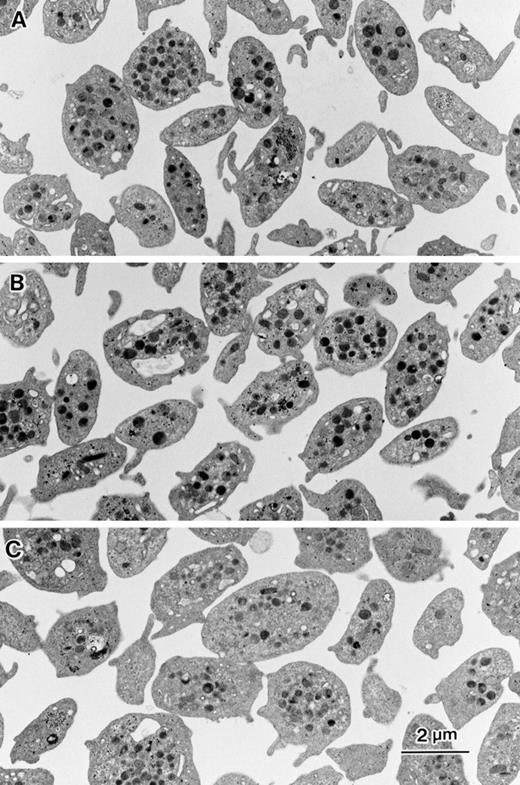

Ultrastructural analysis was performed to evaluate the effects of inhibitors on platelet shape, aggregation, and granule release. Unstimulated platelets showed discoid shape with small and short pseudopodia (Fig 7A). In the presence of 10 μmol/L DCB the platelets maintained discoid shape similar to control platelets (Fig 7B). However, platelets incubated with 80 μmol/L bepridil tended to be round shaped (Fig 7C). Fifteen-minute incubation of thrombin-stimulated platelets in the presence of 0.1% DMSO resulted in the formation of small aggregates (10 to 20 platelets). Each platelet showed pseudopodia formation and granule secretion (Fig 8A). In the presence of 10 μmol/L DCB, both pseudopodia formation and granule secretion were induced by thrombin, whereas the formation of platelet aggregates were markedly reduced (Fig 8B). Bepridil, similar to DCB, strongly inhibited aggregate formation by thrombin (Fig 8C). Although the pseudopodia formation was impaired, the stimulated platelets had no granules in the cytoplasm, suggesting that the release reaction had occurred even in the presence of bepridil (Fig 8C). These ultrastructural analyses confirmed the inhibitory effects of NCX inhibitors on platelet aggregation and also showed that granule secretion induced by thrombin occurred in the presence of NCX inhibitors. Thus, NCX inhibitors, particularly DCB, seemed to make platelets thrombasthenic.

Effects of DCB or bepridil on morphological changes in intact platelets. Washed platelets (5 × 105/μL) were suspended in modified Tyrode Hepes buffer containing 1 mmol/L CaCl2 and mixed with 0.1 % DMSO (A), 10 μmol/L DCB (B), or 80 μmol/L bepridil. After 15 minutes of incubation, equal volume of 4 % glutaraldehyde containing phosphate buffer was added to each aliquot. Electron microscopic analysis was performed as described in Materials and Methods.